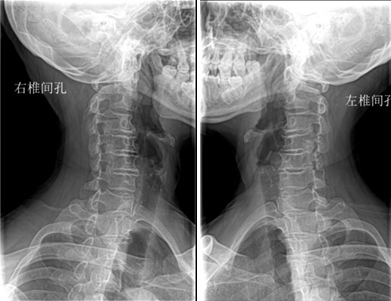

入院后完善各项辅助检查,赖奶奶的颈椎DR显示: 颈椎生理曲度变直;各颈椎椎体骨质完整,C3-6椎体边缘见骨质增生,C3/4、4/5、5/6椎间隙稍变窄,双侧C3/4、4/5、5/6椎间孔变窄;齿状突居中。颈椎MR示:1.颈椎退行性变,椎体欠稳;2.颈3/4、颈4/5、颈5/6椎间盘向后突出;颈4/5水平椎管狭窄,局部颈髓受压变性。

术前DR